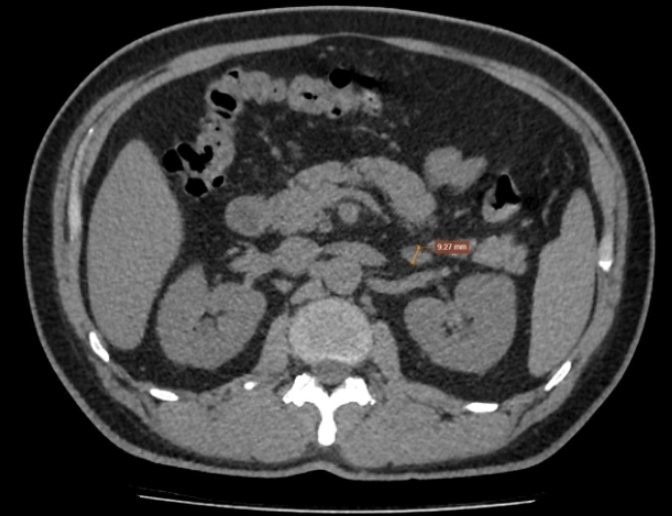

| Phim chụp của bệnh nhân. |

Chụp cắt lớp vi tính tuyến thượng thận phát hiện tuyến thượng thận trái tăng kích thước, bề dày lớn nhất khoảng 13 mm nhưng không thấy khối rõ ràng, gợi ý tăng sản tuyến thượng thận trái. Dựa trên lâm sàng, xét nghiệm và hình ảnh học, bệnh nhân được chẩn đoán xác định hội chứng Conn do tăng sản tuyến thượng thận trái.